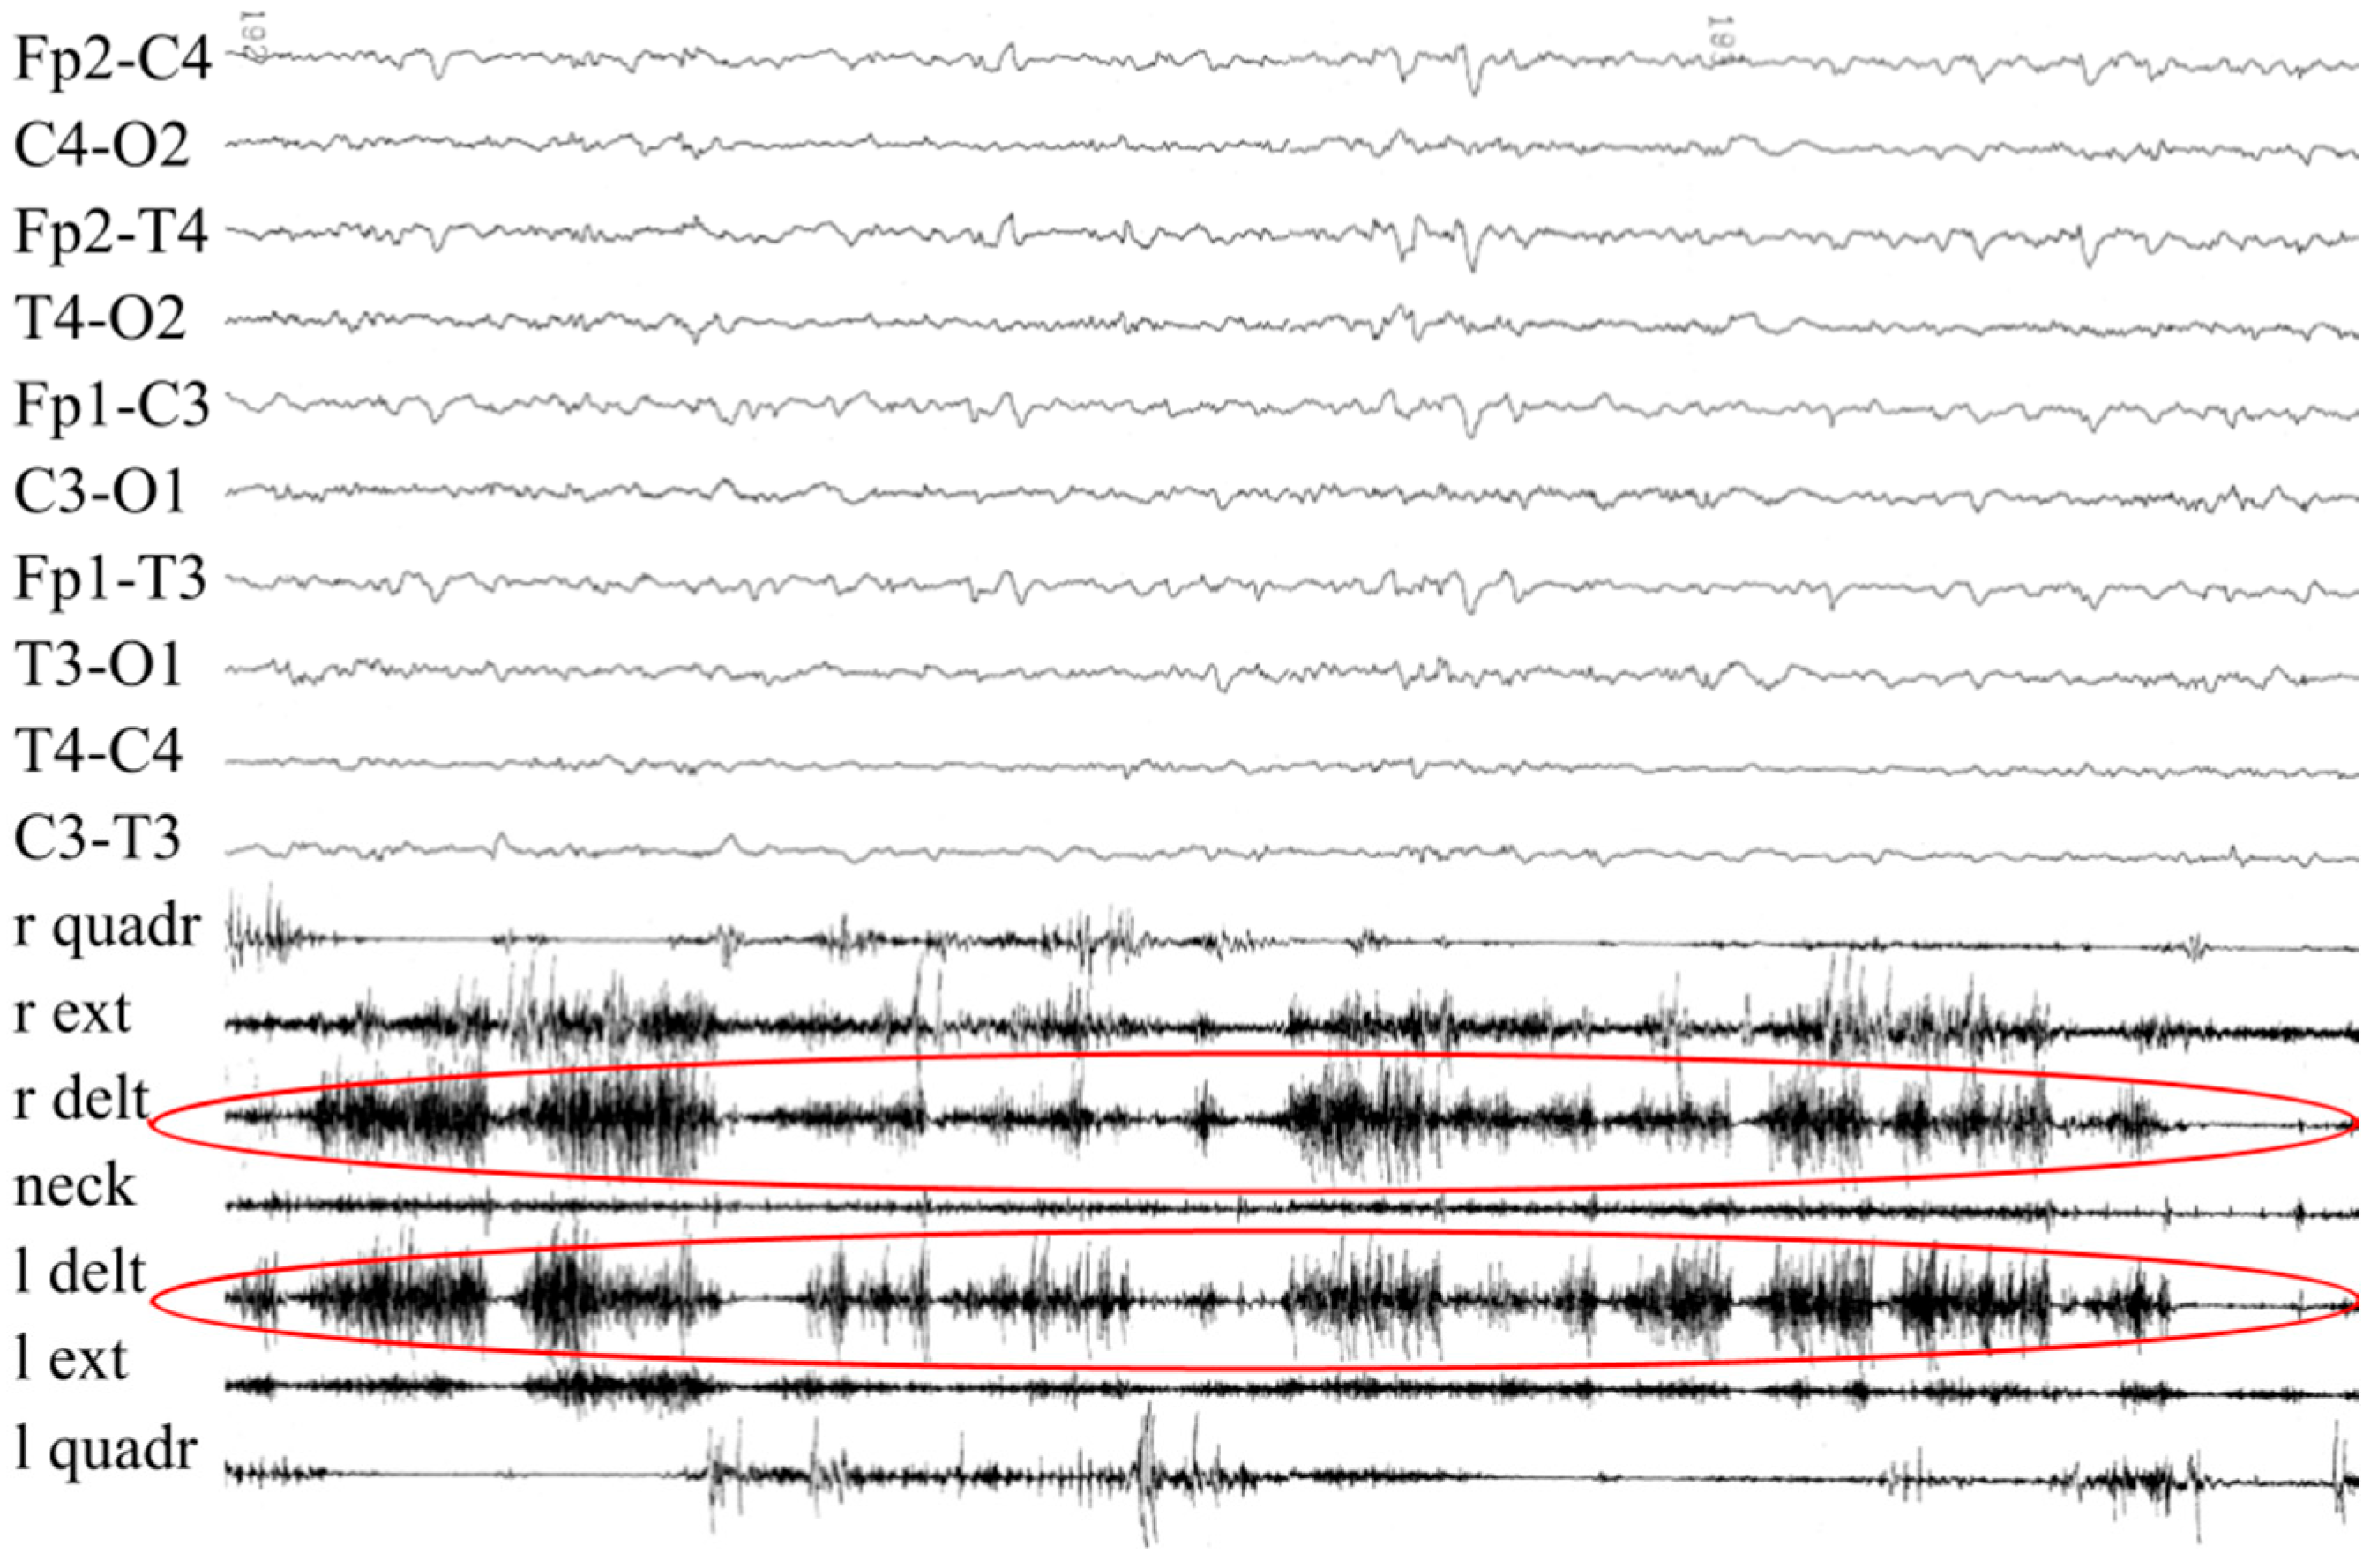

3.2. Patient #2

| Evidence prompting suspicion of cs/ciss | Orofacial muscle contractions, generalized paroxysmal events, camptodactyly | Prenatal bilateral camptodactyly |